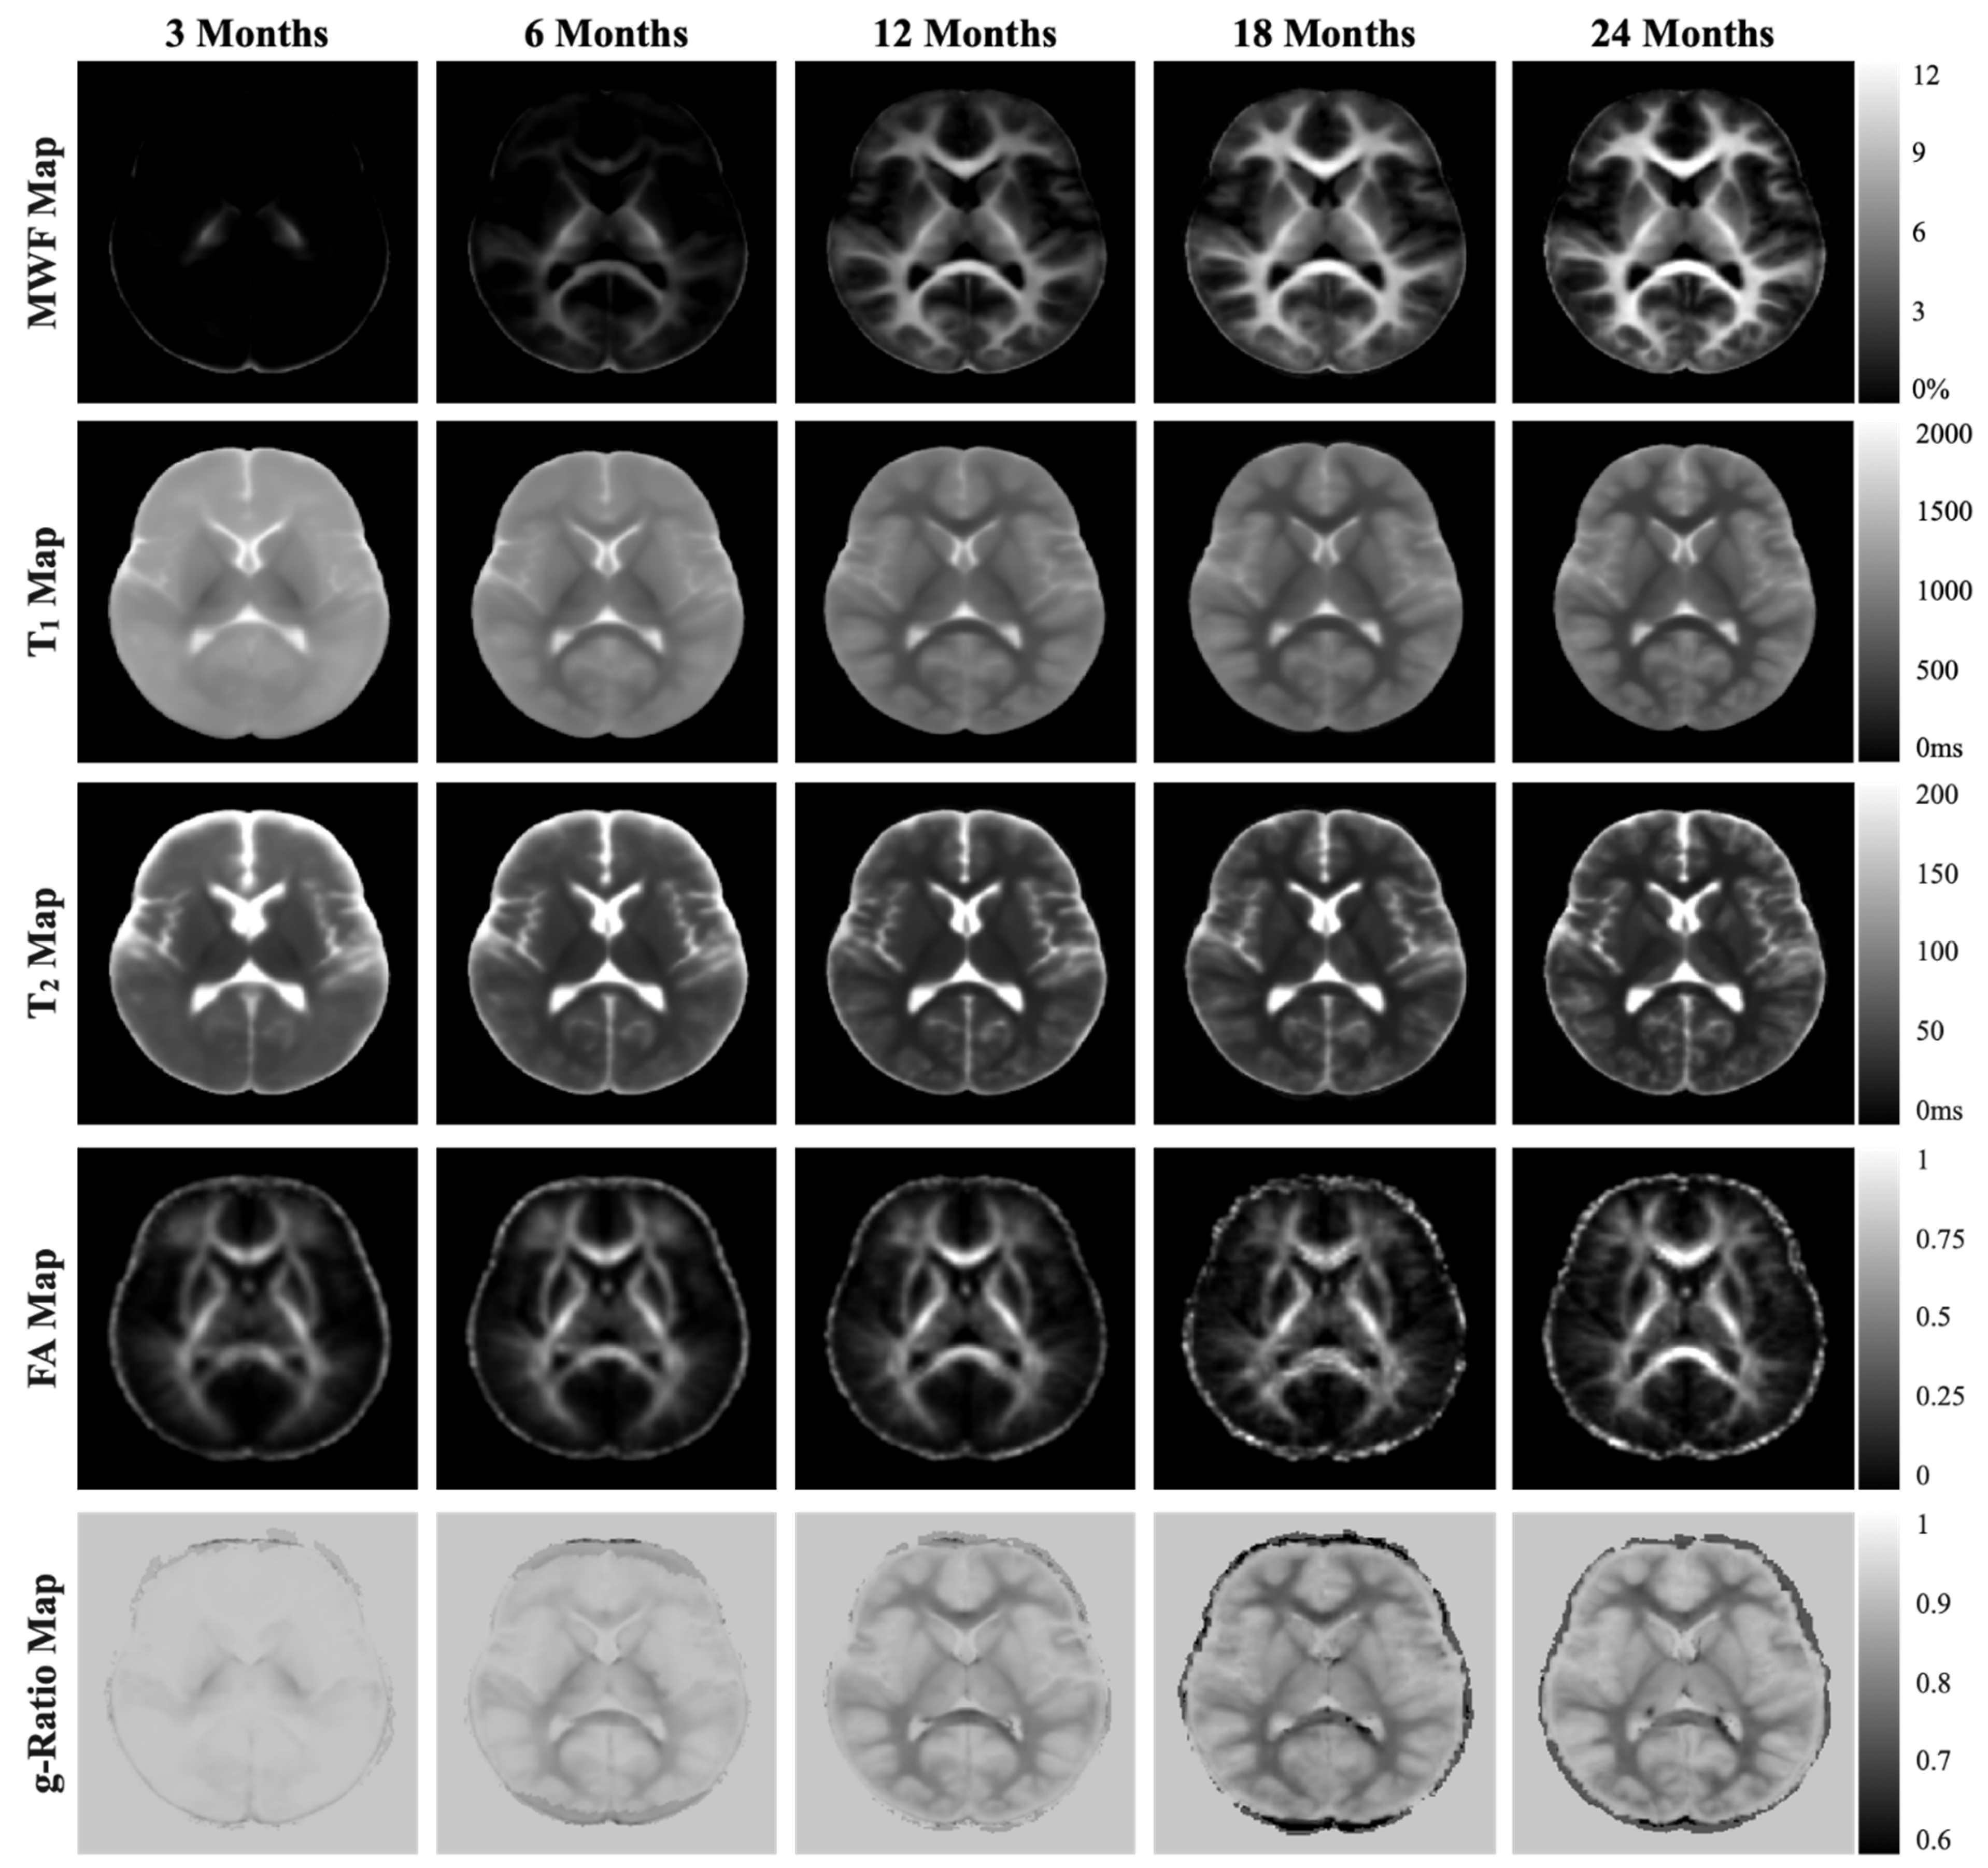

2.4. MRI Assessment

2.4.1. MRI Acquisition Protocol

2.4.2. MRI Analysis

3.3.3. Gray and White Matter Volume (Secondary Outcomes)